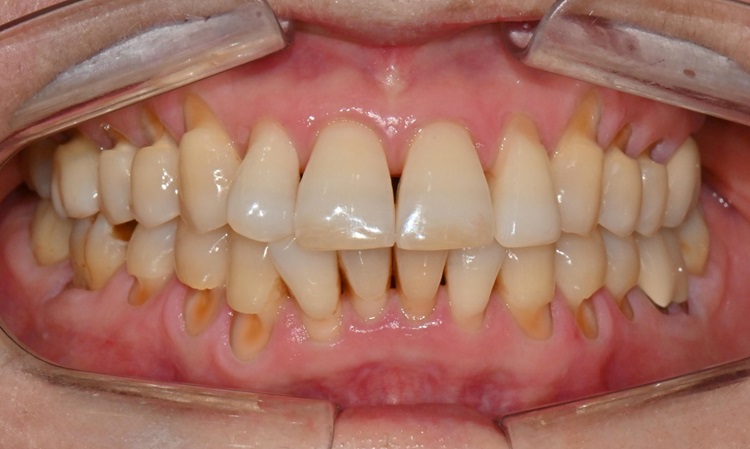

본 환자는 70세 여환으로 가만히 입을 다물고 있을 때 화난 것 처럼 보인다고 해서 튀어나온 앞니를 조금 넣고 싶다는 주소로 내원하셨습니다. 전체적인 치아 및 잇몸 상태를 검진해본 결과, 마모되어 깨진 치아도 있었고, 치경부(치아와 잇몸 사이 경계 부위)가 마모되어 파여 있는 부위도 많았습니다.

2025.2.3. 초진